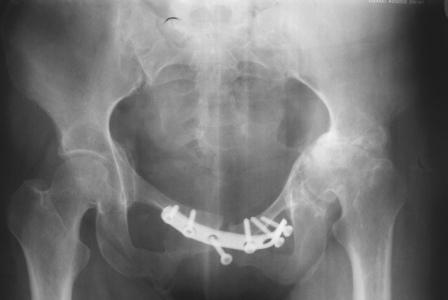

Уважаемые коллеги! Пациентка 32 года с застарелым повреждением таза, после остеосинеза лонного сочленения пластиной. Посоветуйте с выбором тактики и методик лечения.

Получила травму в феврале 2004г в г.Лобытнанги ЯНАО Тюм.обл. Через неделю после поступления выполнен остеосинтез лонного сочленения пластиной. 1,5 месяца на скелетном вытяжении. В последующем ходит при помощи костылей с нагрузкой на правую ногу. Имеется нестабильность половин таза, неправильно-консолидированный перелом левой вертлужной впадины, невропатия седалищного нерва слева. В результате невропатии седалищного нерва сформировалась эквинусная установка левой стопы,парестезии по подошвенной поверхности.

Направлена к нам для устранения патологической установки стопы и эндопротезирования левого тазобедренного сустава, также имеется миграция шурупов пластины, фиксирующей лонное сочленение.

Клинически: ходит на костылях с нагрузкой на правую ногу. Левая стопа в эквинусе. Осевая нагрузка на левую н\конечность болезненна в области левого тазобедренного сустава, при прикосновениях к подошвенной поверхности стопы у пациентки чувство зжения. В левом коленном суставе полный обьем движений, в левом тазобедренном резко ограничено отведение и ротация, укорочение левой н\конечности на 2,5 см. При полипроекционной и функциональной Р-графии выявлена нестабильность левого КПС и лонного сочленения, консолидированный в порочном положении поперечный оскольчатый перелом левой вертлужной впадины с центральным смещением головки бедра. Нами выполнена коррекция деформации левой стопы. Планируется выполнить введение 2 канюлированных илиосакральных винтов слева, реостеосинтез лонного сочленения реконструктивной пластиной, после заживления ран - тотальное эндопротезирование левого тазобедренного сустава.

На сегодняшний день надо уточнить степень сращения впадины, величину дефекта, надо делать кт шаг 2-3мм не больше. Если сращения нет - отдельная песня.

При устанеовке протеза возможное осложнение повторное разобщение фрагментов впадины фрезами.